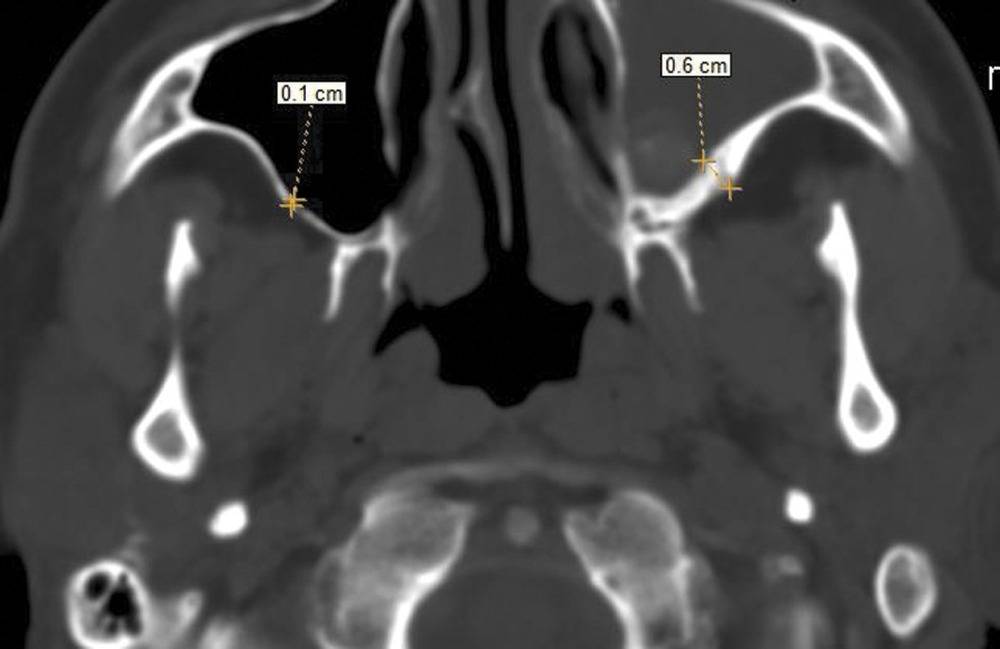

КТ-снимки хронического этмоидита: подробная визуализация